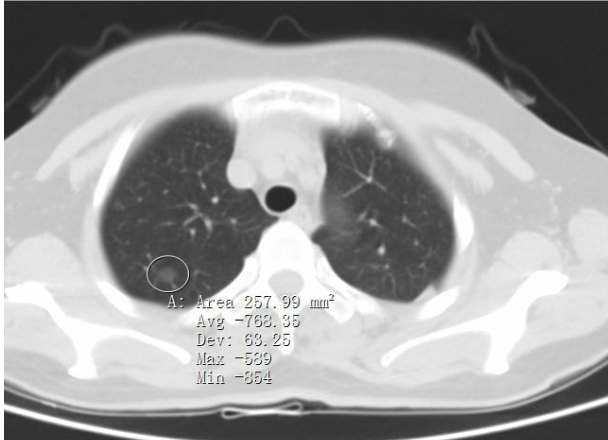

答:通俗的说,肺原位癌指的是发生在支气管或肺上皮层,并且没有突破基底膜的癌。肺原位癌一般肿瘤较小,大小基本上都在1cm以内,胸部CT上多提示为纯磨玻璃结节或混合磨玻璃结节。在临床肿瘤分期中,肺原位癌为0期,属于极早期癌。这类肿瘤细胞生长缓慢,贴壁生长。部分人随访数年,结节并没有明显增大,部分人结节在数年后才加速增长。所以,肺原位癌不用担心短期内出现快速生长,甚至转移到其他地方。

肺原位癌常见CT表现